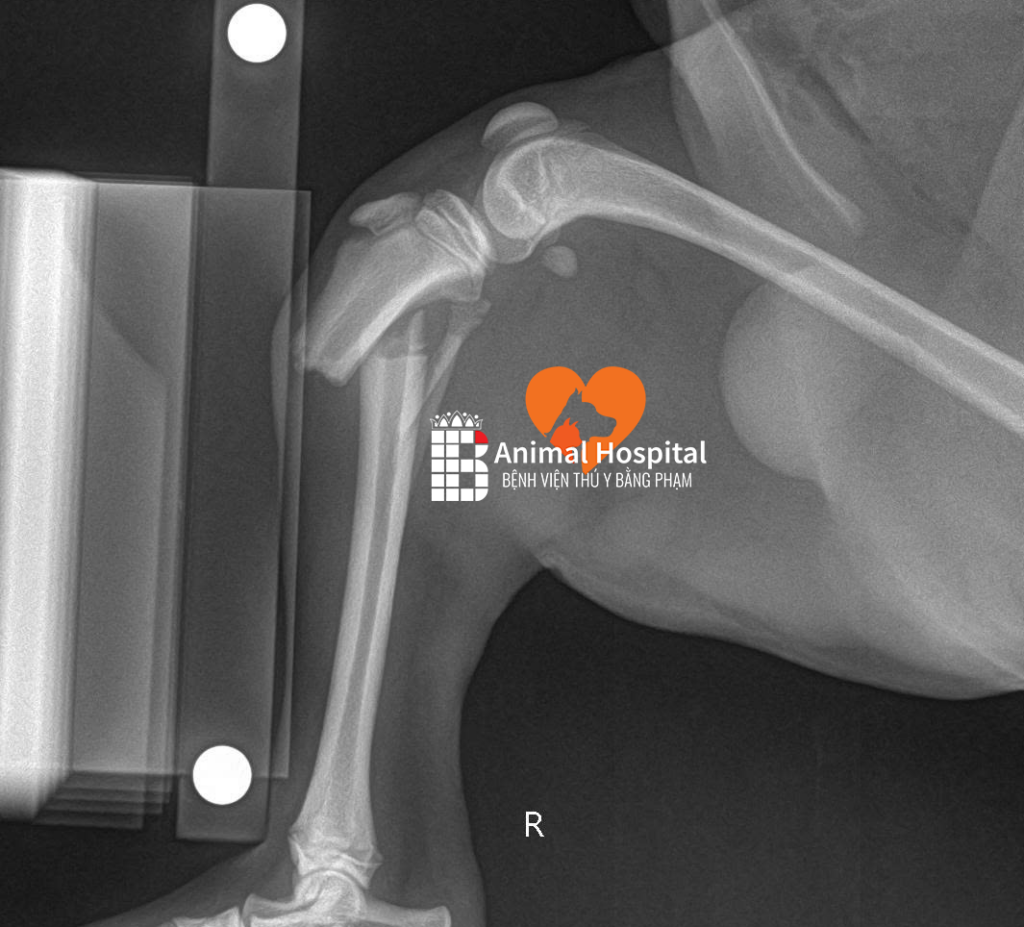

Qua thăm khám khẩn cấp, các bác sĩ xác định bé bị gãy đầu gần xương chày chân phải sau, kèm tổn thương mô mềm nghiêm trọng. Với các trường hợp chó bị cắn gãy chân, chấn thương vật lý thường đi kèm với những tổn thương bên trong. Điều đáng lo ngại hơn là chức năng gan và thận của bé đã bị ảnh hưởng rõ rệt do sốc chấn thương.

Để đảm bảo hiệu quả phục hồi vận động cao nhất cho tình trạng chó bị cắn gãy chân, các bác sĩ bóc tách mô mềm tiếp cận ổ gãy, nắn chỉnh các mảnh xương về đúng trục giải phẫu, sau đó áp dụng hệ thống nẹp vít PRCL, một giải pháp cố định xương tiên tiến giúp giảm thiểu diện tích tiếp xúc giữa nẹp và xương, từ đó bảo vệ nguồn cung cấp máu cục bộ và tạo điều kiện tối ưu cho quá trình liền xương.